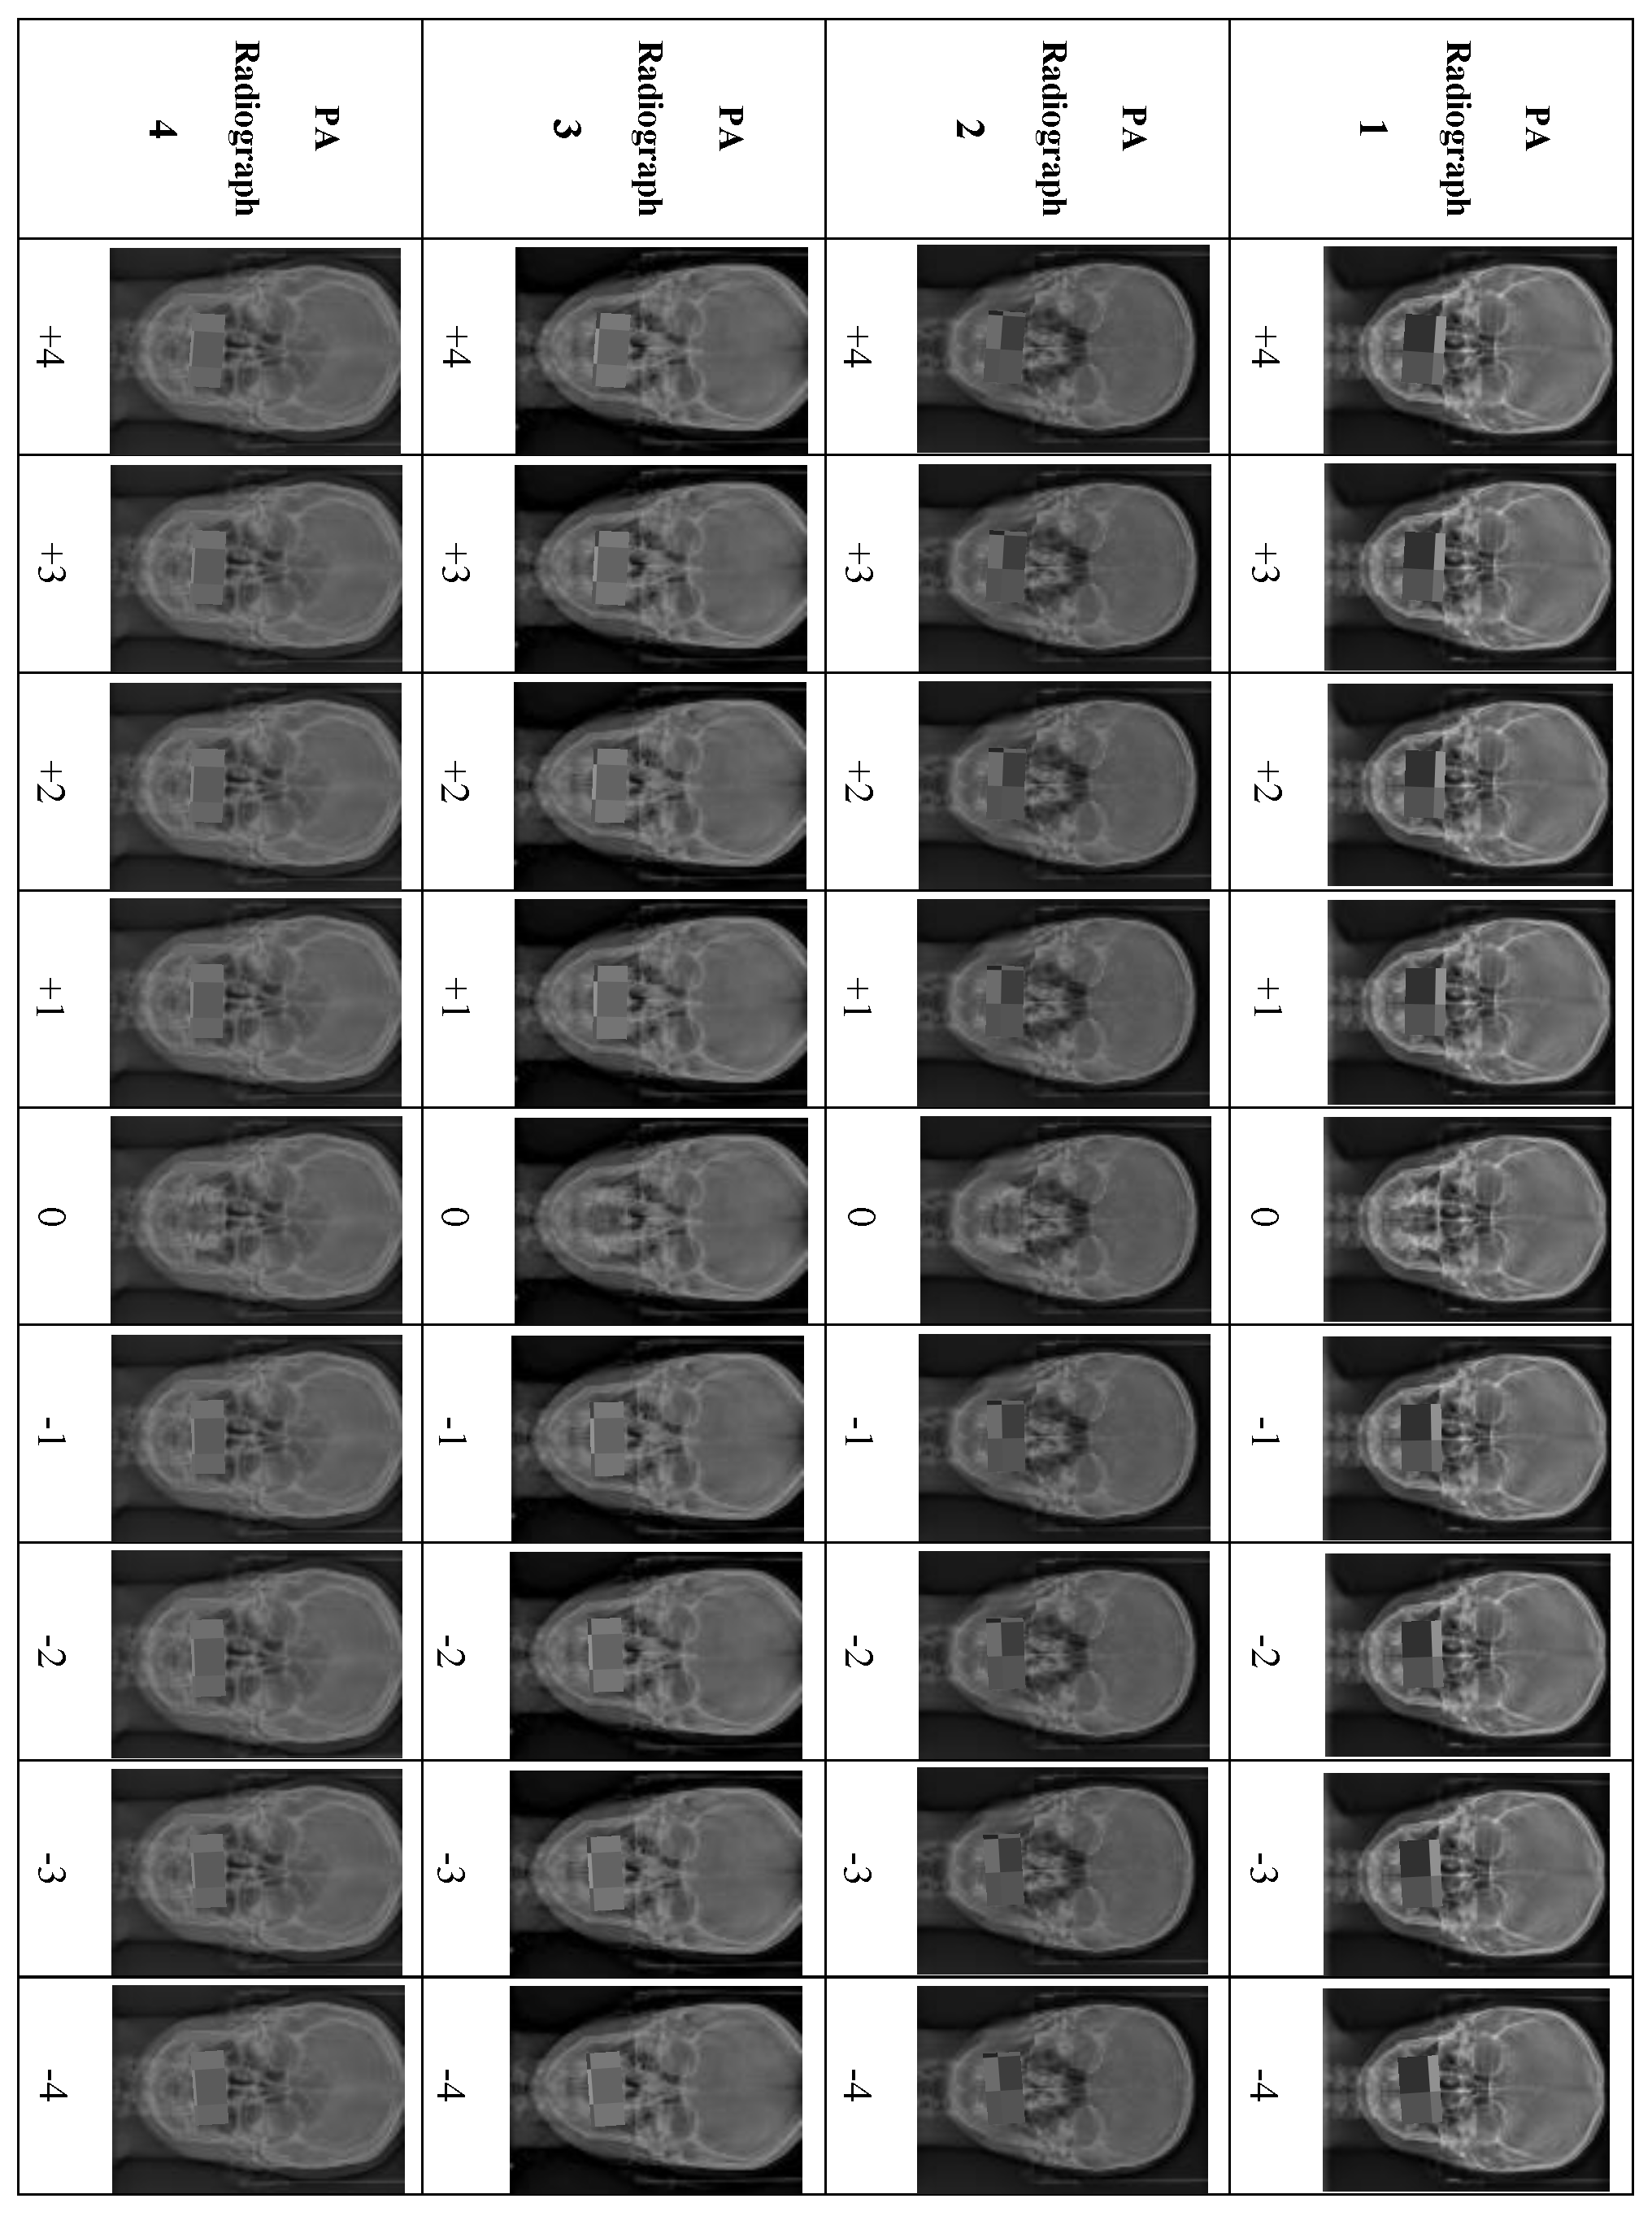

Eighteen PA cephalometric radiographs were excluded because they did not meet the inclusion criteria. Four PA cephalometric radiographs, representing two men and two women, were included in the study. Written informed consent was obtained from the four patients to use their PA radiographs with all the desired manipulations. For each PA radiograph, the upper and lower teeth in occlusion were cropped and manipulated to create different degrees of OC using Photoshop (Adobe Photoshop 9.0, San Jose, CA, USA). For accurate manipulation, the true horizontal line was used as a reference to rotate the OP in each PA image digitally. The OP in the original PA image was rotated in 1° increments from 1° to 4° in both directions. Accordingly, a set of nine manipulated PA images exhibiting various degrees of OCs based on the cut-off points of the newly developed OCI were prepared from each PA image. Each PA radiograph was manipulated to produce eight PA images representing Grades I to III of the OCI, with 1° representing Grade I, 2° and 3° representing Grade II, and 4° of OC representing Grade III (four right-sided and four left-sided), and the ninth manipulated PA image representing Grade 0 (0°). Thus, the four PA radiographs produced 36 manipulated PA images (Figure 1).

Figure 1. Illustration of the manipulations of all the PA cephalometric radiographs, +1° to +5° (OC at the left side), and −1° to −5° (OC at the right side).